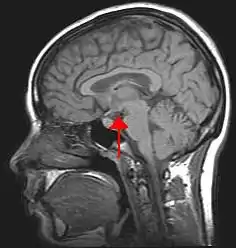

Since the nervous system does not store nutrients, it must receive a continuous supply from blood. Any interruption to the flow of blood may bring brain damage or death. The nervous system maintains homeostasis by controlling and regulating the other parts of the body. A deviation from a normal set point acts as a stimulus to a receptor, which sends nerve impulses to a regulating center in the brain. The brain directs an effector to act in such a way that an adaptive response takes place. If, for example, the deviation was a lowering of body temperature, the effector acts to increase body temperature. The adaptive response returns the body to a state of normalcy and the receptor, the regulating center, and the effector temporarily cease their activities. Since the effector is regulated by the very conditions it produced, this process is called control by negative feedback. This manner of regulating normalcy results in a fluctuation between two extreme levels. Not until body temperature drops below normal do receptors stimulate the regulating center and effectors act to raise body temperature. Regulating centers are located in the central nervous system, consisting of the brain and spinal cord. The hypothalamus is a portion of the brain particularly concerned with homeostasis; it influences the action of the medulla oblongata, a lower part of the brain, the autonomic nervous system, and the pituitary gland.

Most of these organs are controlled by hormones secreted from the pituitary gland, which in turn is directed by the hypothalamus.